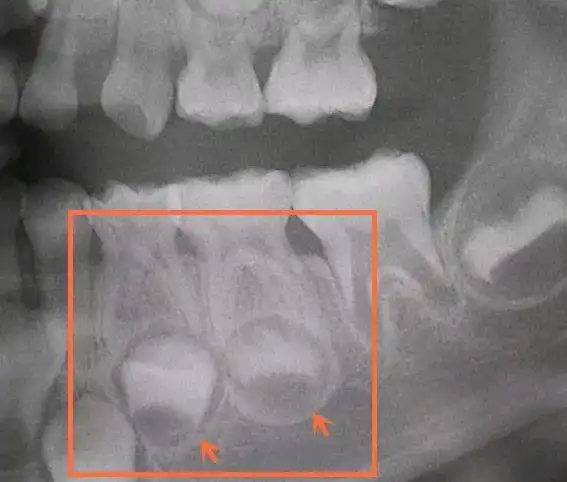

6岁左右少儿的乳牙和恒牙的x光图,前面一排是乳牙,乳牙后面的是还没长

儿童乳牙治疗|牙片分析6015 图1: 左上门牙有龋坏,需要补牙.